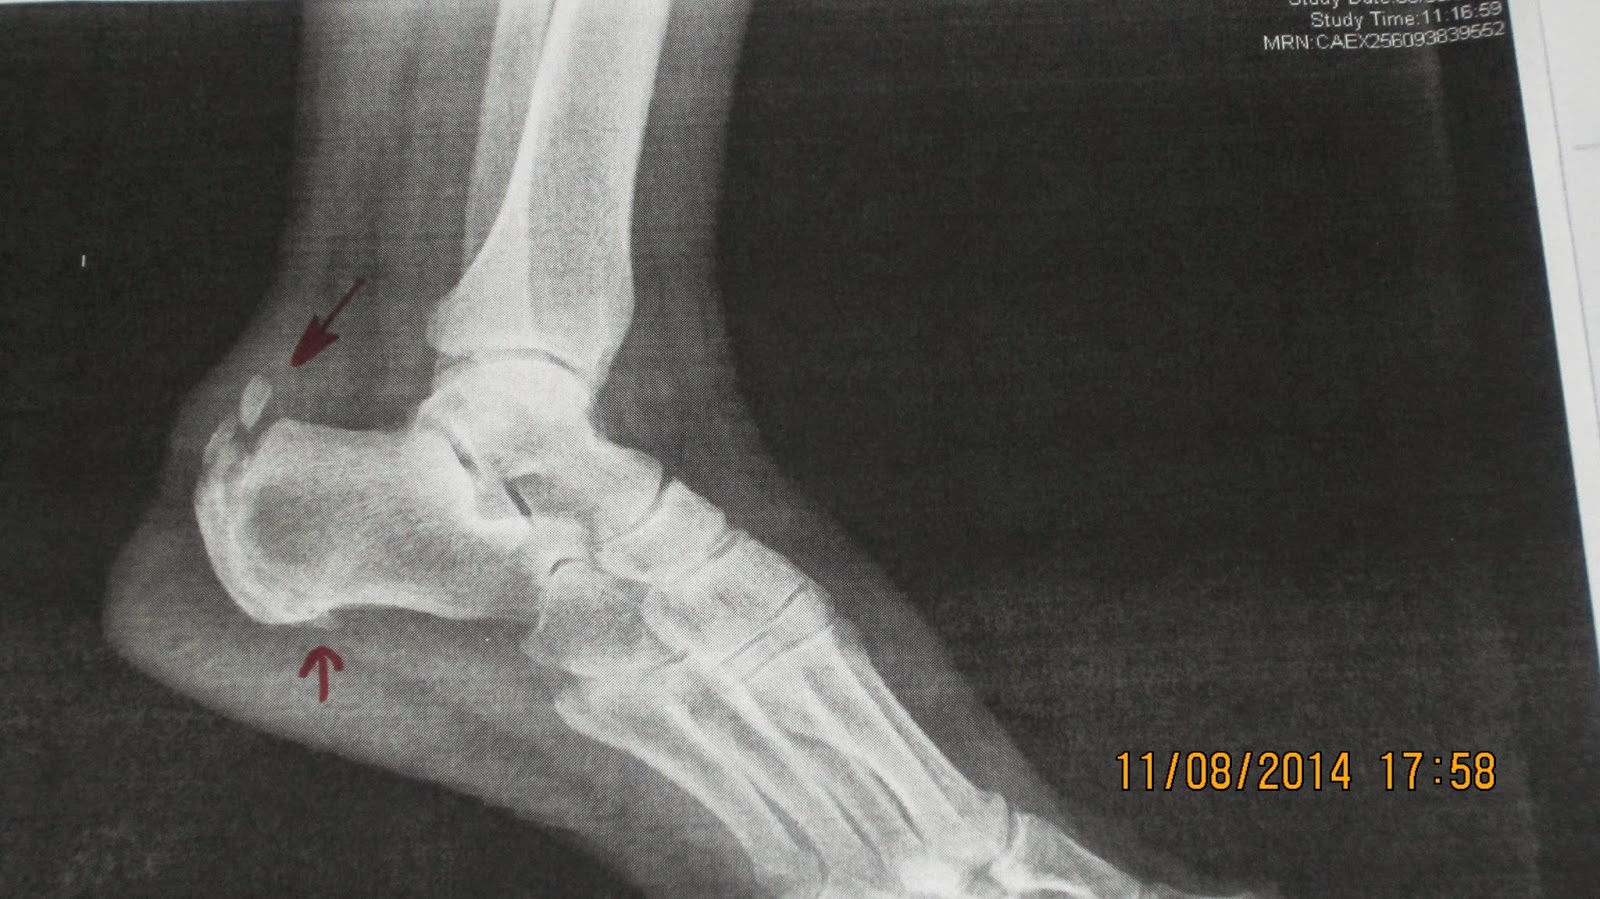

WebLas calcificaciones son muy frecuentes, aunque no siempre son la causa del dolor ya que a veces pueden provenir de la propia inflamación que genera esa calcificación. WebEl tendón de Aquiles o también llamado tendón calcáneo, es un tejido fuerte y resistente de la parte posterior e inferior del miembro inferior que sale de la unión de varios músculos. WebLas principales causas de las calcificaciones en el tendón de Aquiles son: “Una tendinitis/tendinopatia crónica mal curada, un sobreuso y microtraumatismos. WebEl tendón de Aquiles es el encargado de propulsarnos al caminar, correr o saltar. Los tendones son estructuras que unen el músculo al hueso, y el tendón de. WebLa tendinopatía calcificada insercional del tendón de Aquiles (ACIT) es una afección causada por el deterioro del tendón de Aquiles en el talón, que da lugar a. WebCALCIFICACIONES EN EL TENDÓN DE AQUILES. Prentamos el caso clínico de una paciente mujer de 53 años que acudió a nuestra consulta con dolor en el talón derecho. WebEn nuestro estudio hemos detectado radiológicamente (radiografía lateral de rodillas) calcificaciones de los tendones gastrocnemios en el 27,7% de las rodillas evaluadas, lo. WebTratamiento calcificación tendón de aquiles con ondas de choque. Hoy os mostramos un vídeo del tratamiento satisfactorio aplicado a un paciente con una.

WebEn nuestro estudio hemos detectado radiológicamente (radiografía lateral de rodillas) calcificaciones de los tendones gastrocnemios en el 27,7% de las rodillas evaluadas, lo. WebTratamiento calcificación tendón de aquiles con ondas de choque. Hoy os mostramos un vídeo del tratamiento satisfactorio aplicado a un paciente con una.